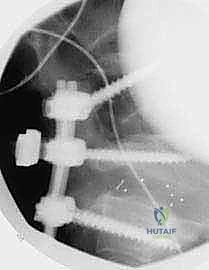

عملية تثبيت الفقرات الخلفي الجانبي تُعتبر "المعيار الذهبي" (Gold Standard) في جراحات العمود الفقري القطني لعلاج حالات الانزلاق الفقاري. تعتمد هذه الجراحة على مبدأ دمج الفقرات غير المستقرة باستخدام طعوم عظمية ومثبتات معدنية من التيتانيوم، مما يمنع الحركة غير الطبيعية بين الفقرات، ويقضي على مصدر الألم.

المعيار الذهبي: عملية تثبيت الفقرات الخلفي الجانبي (Posterolateral Arthrodesis)

عملية تثبيت الفقرات الخلفي الجانبي هي الإجراء الجراحي الأكثر شيوعاً واعتماداً لعلاج الانزلاق الفقاري. الهدف من هذه الجراحة هو إيقاف الحركة المؤلمة بين الفقرات غير المستقرة من خلال دمجها